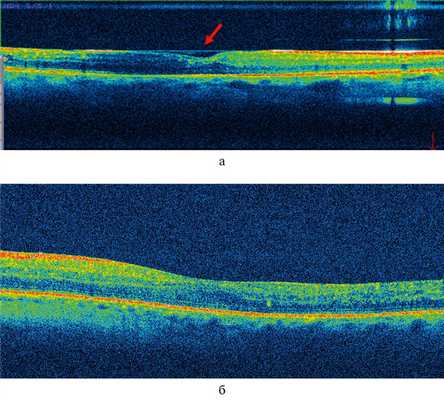

У пациентов 2-й группы была измерена только зона «СНВ» в связи с отсутствие ВПМ и в среднем составила 28,41±1,88 мкм (р1—2 <0,05). ЭРМ и тракционный отек МО не диагностировались ни в одном случае, однако у данных пациентов в период от 1 до 3 мес (до удаления СМ) на В-сканах ОКТ визуализировалась гиперрефлективная линия над МО (рис. 2, а). Рис. 2. В-скан ОКТ макулярной области пациента К. а — в течение 3 мес после витрэктомии в сочетании с пилингом внутренней пограничной мембраны на фоне силиконовой тампонады (красной стрелкой указано на гиперрефлективную линию над макулярной областью, без тракционного компонента); б — через 3 мес после витрэктомии в сочетании с пилингом внутренней пограничной мембраны, после удаления силиконового масла из витреальной полости. Ранее визуализируемая (рис. 2, а) гиперрефлективная линия над макулярной областью полностью отсутствует.

Всем пациентам 2-й группы было проведено удаление СМ с последующей воздушной тампонадой. При контрольных осмотрах, по данным ОКТ, ранее визуализируемая гиперрефлективная линия полностью отсутствовала (см. рис. 2, б). После удаления СМ в этой группе в течение оставшегося срока наблюдения (3 мес) у 5 пациентов произошли кровоизлияния в витреальную полость в виде мазков гемы, которые успешно купировались на фоне консервативной терапии.